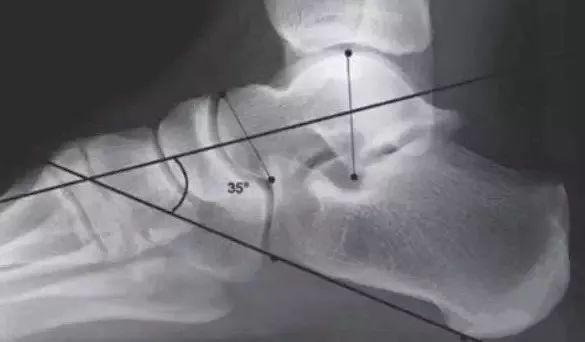

影像学检测

侧位跟距角:由距骨头部中点、距骨颈部中点连线与跟骨下缘切线组成;正常为25~45°,大于45°表示后足外翻,意味着后足部分足弓下降。